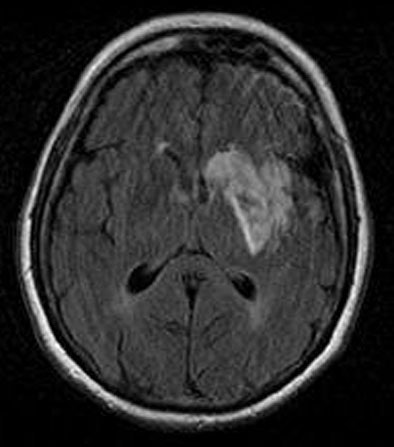

![]() |

| Diffusion-weighted MRI obtained immediately after perfusion CT demonstrates only a slightly hyperintense region in the left basal ganglia. Images courtesy of Dr. Sotirios Bisdas. |